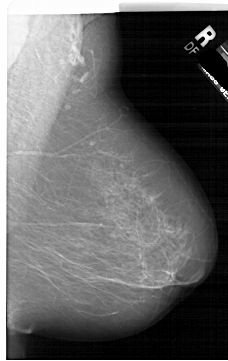

A_1952_1.RIGHT_CC

RIGHT_CC LINES 5791 PIXELS_PER_LINE 3976 BITS_PER_PIXEL 12 RESOLUTION 43.5 NON_OVERLAY